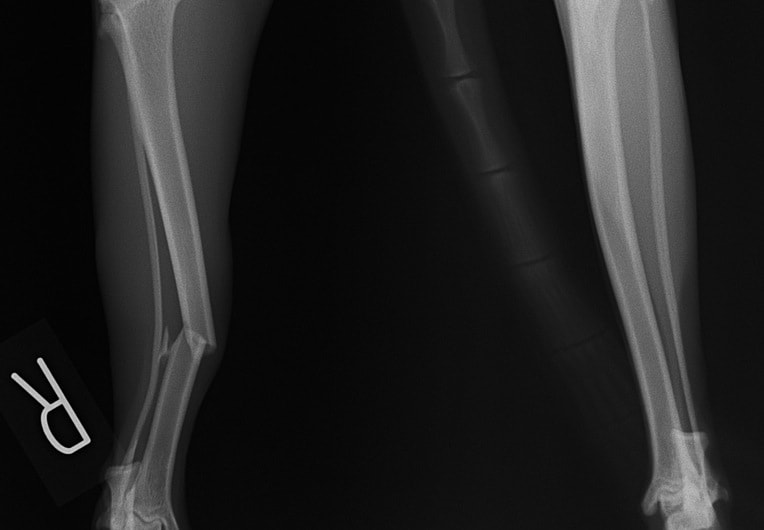

ペルシャ猫 11ヶ月齢 雄

他院にて左大腿骨遠位の成長板骨折(salter-harrisⅠ型)が認められており、治療相談を目的として来院。当院にて、キルシュナーワイヤーを用いたピンニングにより骨折部位の整復を行いました。術後の経過は良好で、現在も経過観察中です。

術前レントゲン